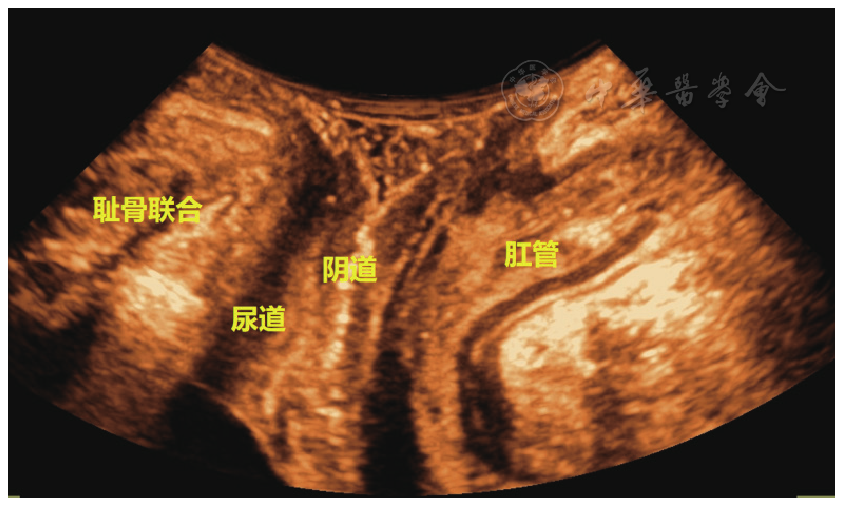

操作前先点击盆底超声预设模式,将三维腹部容积探头置于患者阴道口并紧贴皮肤,嘱受检者放松,动作尽可能轻柔。取盆底正中矢状切面,从前到后清晰显示SP、尿道、膀胱、阴道、肛管等结构(图1)。启动"3D"按钮,首先得到受检者静息状态下盆底结构的原始三维容积图像并储存在机器上。接着指导受检者做2~3次最大Valsalva动作并坚持直至在盆底正中矢状切面完成原始图像采集,获取每位受检者最大Valsalva动作时的最佳图像并储存在机器上。

图1 标准的盆底正中矢状切面盆底超声图像